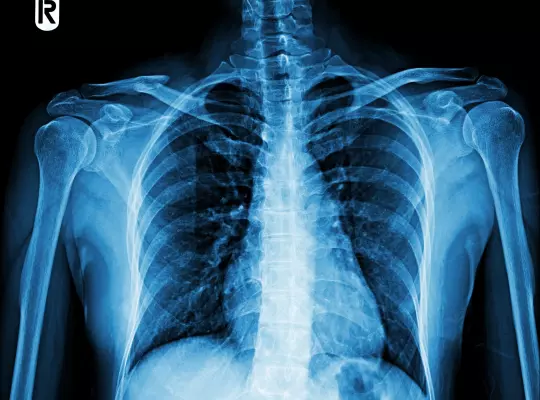

RTG (Badanie Rentgenowskie)

jest przede wszystkim bezbolesne oraz bezinwazyjne. Po wejściu do gabinetu pacjent proszony jest o odsłonięcie prześwietlanego fragmentu ciała i przyjęcie odpowiedniej pozycji, aby umożliwić wykonanie jak najlepszego zdjęcia RTG. Następnie osoba wykonująca prześwietlenie wychodzi do innego pomieszczenia i stamtąd obsługuje aparaturę. W zależności od rodzaju badania Pacjent może być poproszony o chwilowe wstrzymanie oddechu.

RTG klatki piersiowej — łańcuszek